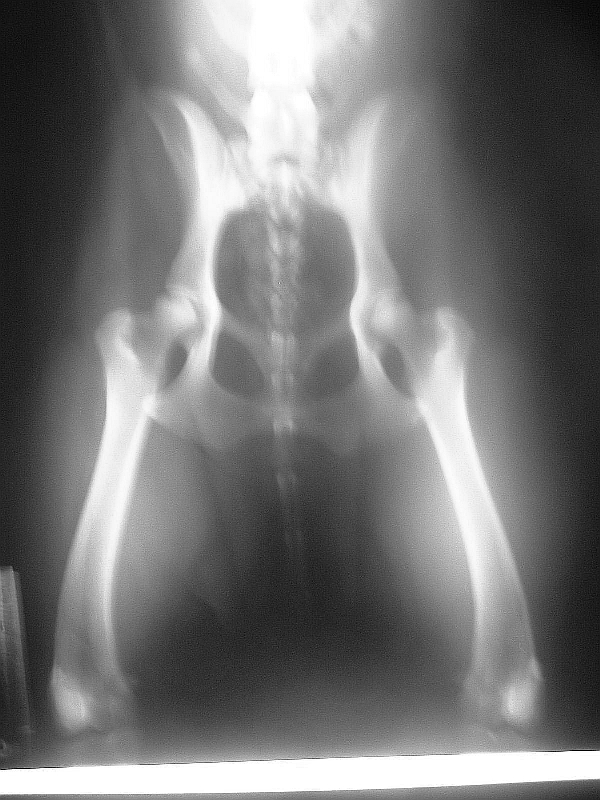

Hip & Elbow Radiographs

OVC Certificate # 0032917 Clear @ 20 months